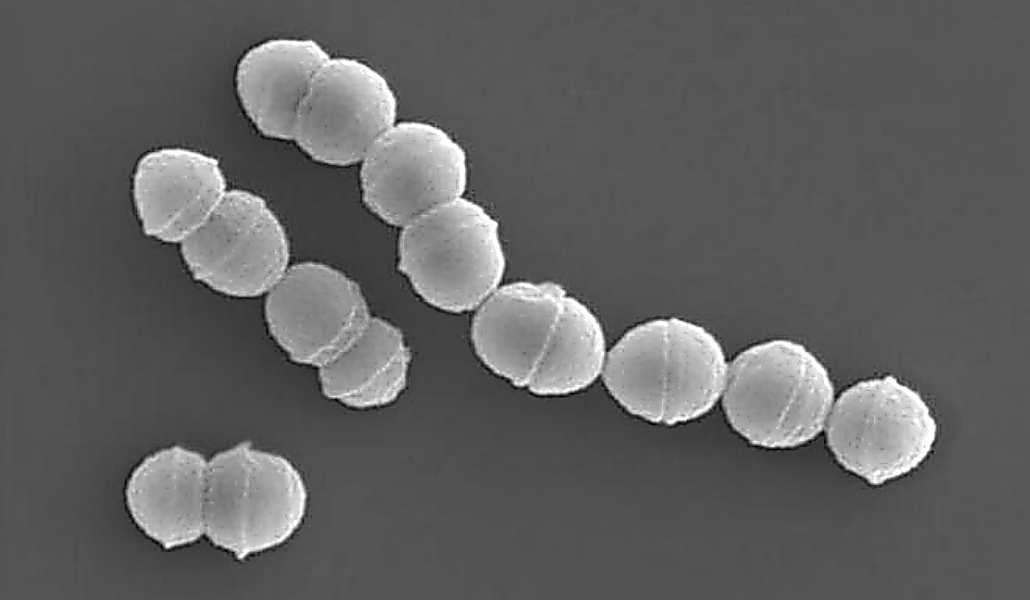

Una de las causas de las infecciones estreptocócicas hemolíticas fulminantes es el «estreptococo hemolítico del grupo A», un tipo de bacteria que se encuentra a menudo en la garganta y la piel, que provoca la necrosis de las extremidades, provocando la muerte por fallos en varios órganos.